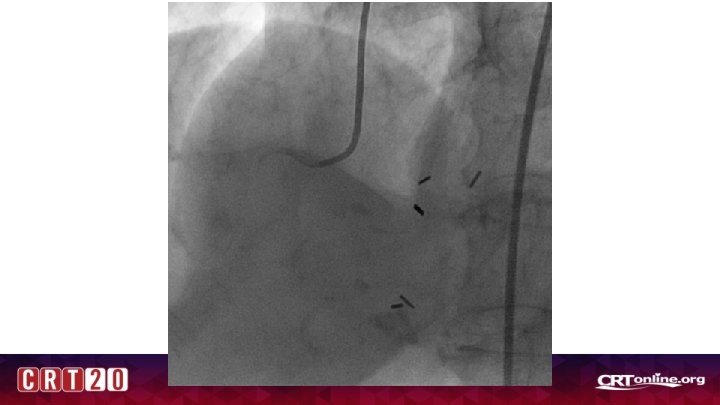

Case 1 • 77 yr old WF with PMN of osteoarthritis, osteoporosis, renal mass being monitored closely, hypothyroidism who presented with weakness, nausea, and atypical chest pain. Had several months of nonspecific periodic nausea leading up to admission. • BP 170/70, HR 75 • EKG: NSR, Normal EKG • Hgb 11. 3, Plt 195 • Cr 0. 80 • Trop 3. 00 > 3. 78 > 3. 66 • Referred for coronary angiogram for NSTEMI

Where is the culprit?